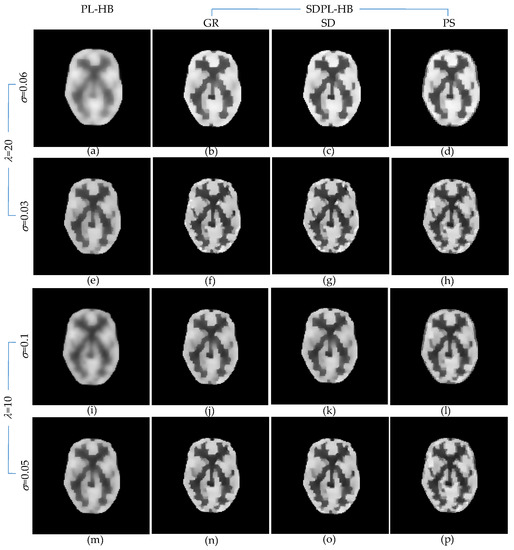

3.1. Numerical Studies Using Digital Phantom

3.2. Qualitative Validation Using Physically Acquired Data

| = 40 = 0.1 | PSNR(dB) | 13.943 | 15.569 | 15.621 | 14.999 |

| SSIM | 0.821 | 0.872 | 0.874 | 0.854 | |

| VIF | 0.404 | 0.540 | 0.547 | 0.531 | |

| MAE | 0.090 | 0.068 | 0.068 | 0.071 | |

| RMSE | 0.201 | 0.167 | 0.166 | 0.178 | |

| MPE | 36.651 | 30.396 | 30.216 | 32.459 | |

| = 40 = 0.03 | PSNR(dB) | 15.475 | 17.133 | 17.232 | 16.856 |

| SSIM | 0.869 | 0.910 | 0.912 | 0.905 | |

| VIF | 0.539 | 0.675 | 0.688 | 0.672 | |

| MAE | 0.069 | 0.051 | 0.050 | 0.052 | |

| RMSE | 0.168 | 0.139 | 0.138 | 0.144 | |

| MPE | 30.728 | 25.387 | 25.101 | 26.210 | |

| = 20 = 0.15 | PSNR(dB) | 14.659 | 16.186 | 16.222 | 15.756 |

| SSIM | 0.843 | 0.887 | 0.887 | 0.876 | |

| VIF | 0.474 | 0.593 | 0.598 | 0.590 | |

| MAE | 0.079 | 0.061 | 0.061 | 0.063 | |

| RMSE | 0.185 | 0.155 | 0.155 | 0.163 | |

| MPE | 33.754 | 28.311 | 28.194 | 29.748 | |

| = 20 = 0.05 | PSNR(dB) | 16.001 | 17.543 | 17.601 | 17.151 |

| SSIM | 0.882 | 0.919 | 0.920 | 0.913 | |

| VIF | 0.587 | 0.720 | 0.730 | 0.706 | |

| MAE | 0.063 | 0.047 | 0.046 | 0.050 | |

| RMSE | 0.159 | 0.133 | 0.132 | 0.139 | |

| MPE | 28.922 | 24.217 | 24.056 | 25.335 | |

| λ = 20 σ = 0.06 | PSNR(dB) | 13.857 | 15.798 | 16.239 | 15.421 |

| MSSIM | 0.823 | 0.880 | 0.889 | 0.868 | |

| VIF | 0.401 | 0.574 | 0.611 | 0.567 | |

| MAE | 0.091 | 0.064 | 0.059 | 0.065 | |

| RMSE | 0.203 | 0.162 | 0.154 | 0.169 | |

| MPE | 37.018 | 29.605 | 28.142 | 30.920 | |

| λ = 20 σ = 0.03 | PSNR(dB) | 15.838 | 17.277 | 17.353 | 17.134 |

| SSIM | 0.880 | 0.914 | 0.916 | 0.912 | |

| VIF | 0.569 | 0.697 | 0.710 | 0.691 | |

| MAE | 0.064 | 0.049 | 0.049 | 0.050 | |

| RMSE | 0.162 | 0.137 | 0.136 | 0.139 | |

| MPE | 29.469 | 24.971 | 24.755 | 25.386 | |

| λ = 10 σ = 0.1 | PSNR(dB) | 14.387 | 16.176 | 16.149 | 15.974 |

| SSIM | 0.837 | 0.888 | 0.887 | 0.883 | |

| VIF | 0.450 | 0.606 | 0.607 | 0.615 | |

| MAE | 0.083 | 0.059 | 0.059 | 0.059 | |

| RMSE | 0.191 | 0.155 | 0.156 | 0.159 | |

| MPE | 34.826 | 28.346 | 28.434 | 29.011 | |

| λ = 10 σ = 0.05 | PSNR(dB) | 15.564 | 17.086 | 17.086 | 16.938 |

| SSIM | 0.872 | 0.909 | 0.909 | 0.908 | |

| VIF | 0.550 | 0.684 | 0.689 | 0.688 | |

| MAE | 0.067 | 0.050 | 0.050 | 0.051 | |

| RMSE | 0.167 | 0.140 | 0.140 | 0.142 | |

| MPE | 30.412 | 25.526 | 25.527 | 25.963 | |